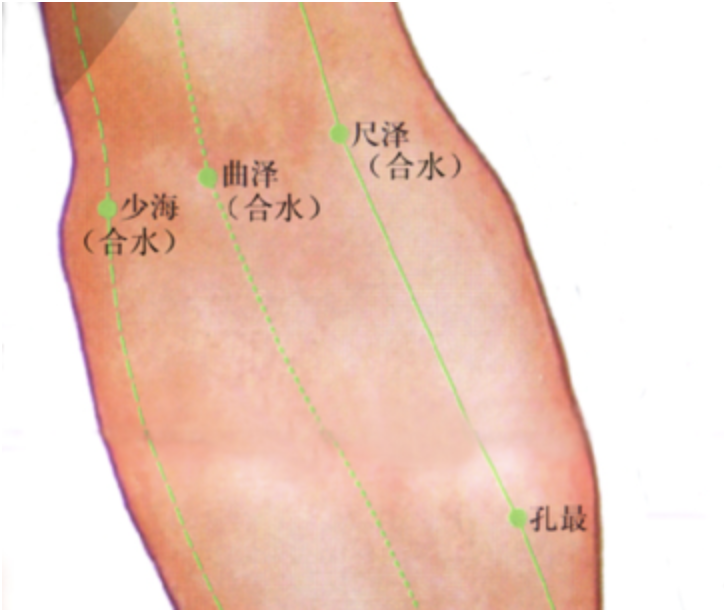

尺泽

【定位】 在肘横纹中,肱二头肌腱桡侧凹陷处(图 10-19-2)。

曲泽

【定位】 在肘横纹中,当肱二头肌腱的尺侧缘(图 10-27-2)。